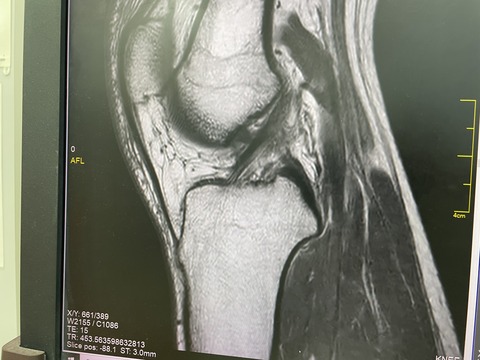

全日本モトクロスプロライダー

膝の怪我にも負けず、

今週末は、大阪の名阪での大会出場です

何とか靭帯損傷を免れましたが、

膝が曲がらない状態での出場を決意

ドーピングがあることから、ステロイド注射は使えず

テーピング、ハムストリング 及び 膝蓋骨周囲の、

タイトネスを取る筋膜リリースをして

レースに臨みます